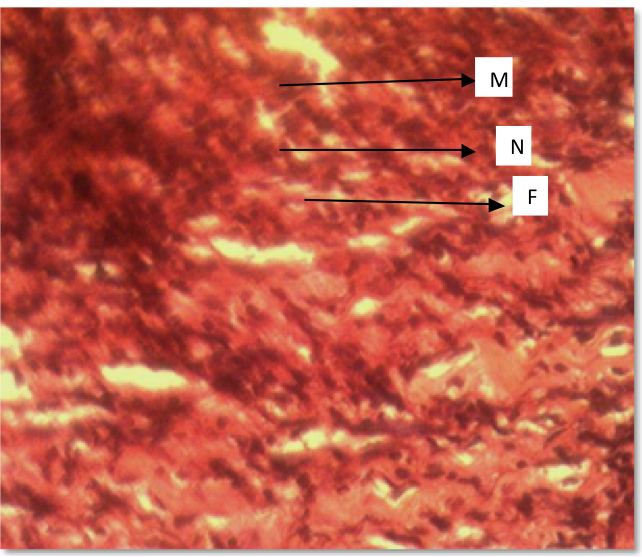

Plate1: Plate showing photomicrograph of control animals on day 9; H&E x200. The section of the skin shows moderate fibrosis, marked with infiltration of neutrophils and macrophages.

Plate1: Photomicrograph of control day 9: H&E x200; (F) = Fibrosis, (M) = Macrophage (N) = Neutrophil